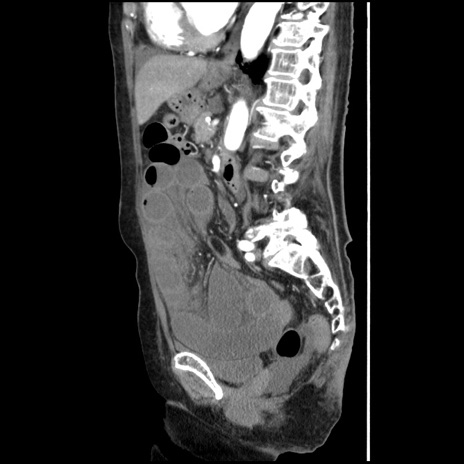

横断像

【症例】80歳代女性

【主訴】腹痛

【現病歴】8時間前から腹痛あり来院。

【既往歴】糖尿病、脂質異常症、子宮体癌にて子宮全摘術

【身体所見】意識清明・会話良好だが腹痛で苦悶様、全腹部にわたって反跳痛と圧痛あり

【データ】WBC 13600、CRP 0.14、LDH 224、CK 90